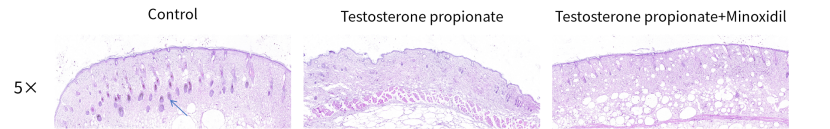

Fig 2. Representative images of HE pathological results. Blue arrow means normal hair follicle.

南模生物成功构建了丙酸睾酮诱导的雄性脱发小鼠模型,所有模型小鼠均观察到明显的脱发症状,且在使用米诺地尔酊的情况下脱发程度得到了一定程度的改善。